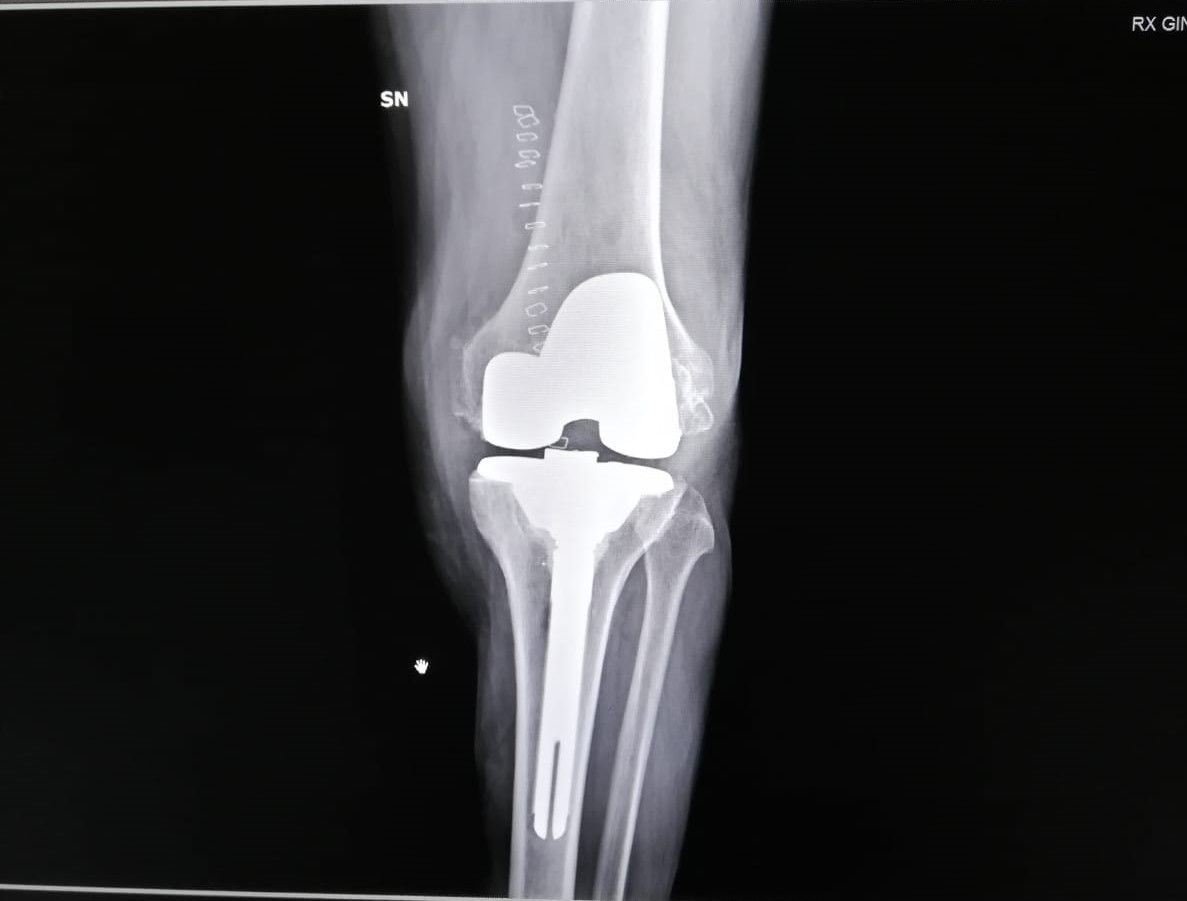

- protesi totale di ginocchio

- protesi mono-compartimentale del ginocchio

Dopo due anni di tentativi vani e aver consultato vari ortopedici, finalmente il dr.Zornetta mi ha illustrato bene la situazione del mio ginocchio. Persona che subito ti trasmette fiducia, competenza e finalmente ti spiega con chiarezza cosa hai, che dire e' una persona semplice e simpatica. Cosi' dopo gli ultimi esami mi ha consigliato l intervento al ginocchio con mezza protesi, mi sono fidata di lui anche perche' mi avrebbe operata lui stesso. A me e' andata tutto bene e lo ringrazio!

Medico competente e preparato, presente durante il ricovero e successivamente, nel mio caso protesi ginocchio. Disponibile e gentile. Esperienza positiva.

Il dottor Zornetta mi ha spiegato molto chiaramente tutti i punti che hanno portato alle operazioni per le protesi a entrambe le ginocchia. Presente anche nel post operazione. Sono molto contenta dei risultati e consiglio vivamente questo dottore.

Ottimo ortopedico,ti segue sino alla fine della operazione e oltre.quando hai bisogno,c'è.ho fatto 2 protesi ai ginocchi da lui.